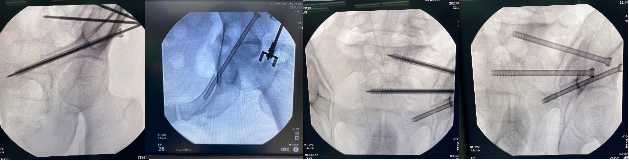

手术当天,骨科治疗组组长何罕亮副主任团队先采用我院先前引进的二代O臂机,现场拍摄患者的骨盆图像,上传至骨科机器人电脑中,经过机器人精密处理,患者的骨折三维图像直观地呈现在了所有人面前。随后,何主任根据图像,实时进行手术规划,选择最佳置钉通道。手术方案规划完毕后,手术机器人机械臂根据制定好的路线精准定位,将误差控制在1mm之内,医生不必切大切口,只需通过3个几毫米的切口便可将螺钉精准打入狭长的耻骨中,如此一来也不会损伤重要的血管神经组织。一旦通道确定,整个置钉过程不过短短几分钟,手术出血不足10ml,精准的置钉操作让医生不必担心需要反复调整而导致钉道松动。术后透视确认了螺钉位置准确无误,手术圆满成功,病人术后恢复满意。

机械臂宛如骨科医生的第三条手臂

机器人精准、智能、高效